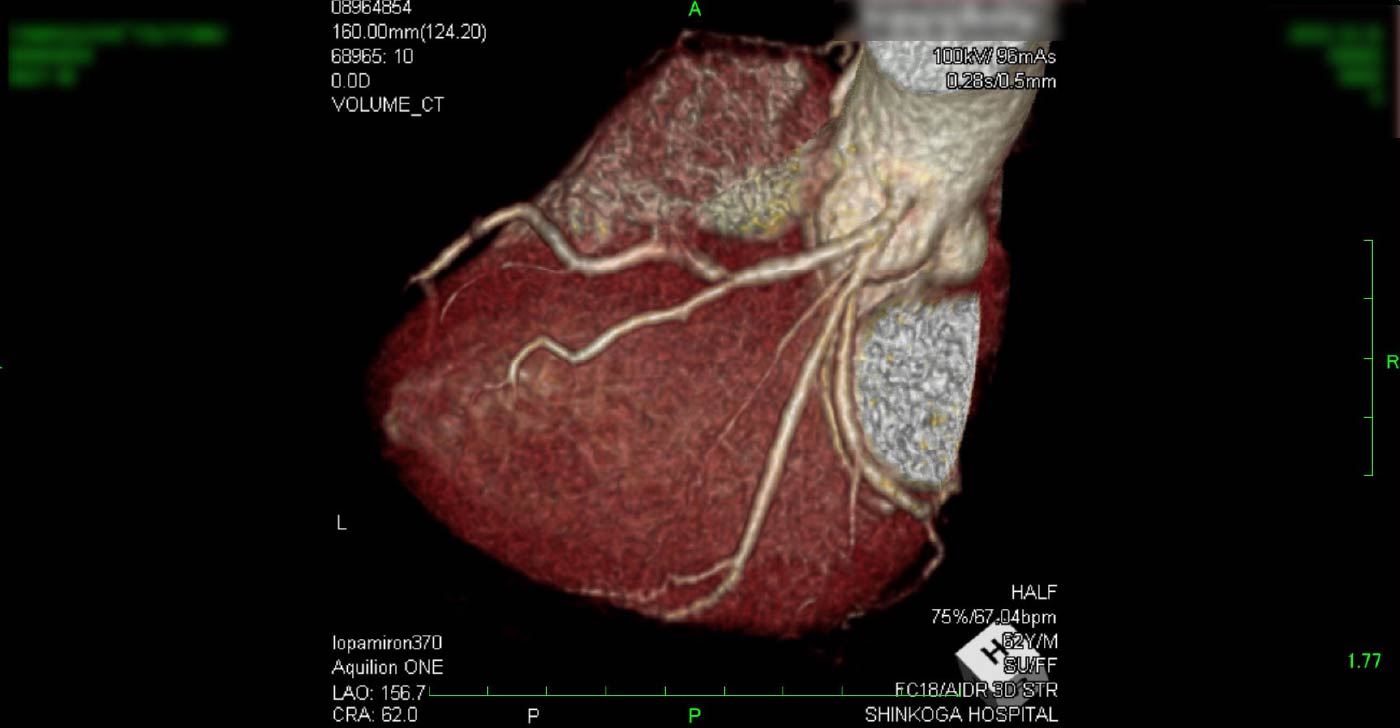

進行期 造影心臓CT 重症心筋虚血症例

冠動脈CT

狭心症を安全に診断あるいは除外する!

連携施設の新古賀病院で速やかに実行可能です。